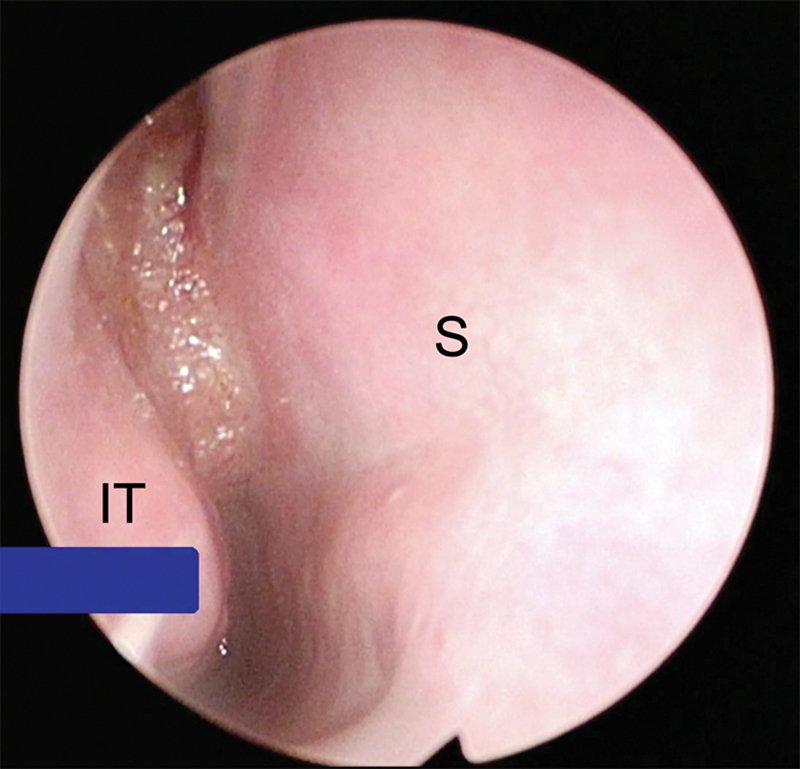

Human papillomavirus (HPV)-associated sinonasal squamous cell carcinoma (SNSCC) (HPV+ SNSCC) is a recently recognized entity that accounts for up to one-third of SNSCC. Although at present these cancers are not routinely tested for HPV, the incidence is increasing and HPV+ SNSCC is associated with superior survival outcomes compared with HPV- SNSCC. Here, we present the case of a patient with HPV+ SNSCC treated with endoscopic resection followed by postoperative radiation and review the literature summarizing epidemiology and management of this disease, with emphasis on the importance of HPV testing in SNSCC.